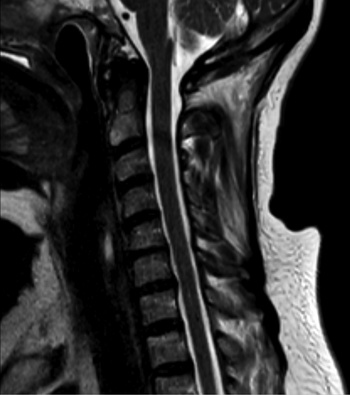

Az ionizáló sugárzással nem járó magnetikus rezonancia (MR) vizsgálat szintén közkedvelt képalkotó eljárás prospektív ikervizsgálatok esetén (3. a, b ábra). Számos területen, főleg a neuroradiológiában alkalmazzák ikrekben. Egyik MR kutatási terület a diffúziós tenzor képalkotás (DTI), melynek során azt vizsgálják, milyen mértékben befolyásolják a genetikai tényezők az agyi kapcsolatokat különböző agyi területeken. A DTI-rekonstrukcióból származó frakcionált anizotrópia tizenegy nagy fehérállományi pálya esetében nagyon örökletesnek bizonyult (Kochunov et al., 2015). Az MR-vizsgálat a T1-szekvencián magas jelintenzitást mutató zsírréteg megítélésére is kiválóan alkalmas. Ezt használták ki egy ausztrál ikervizsgálat során, ahol MR segítségével kapcsolatot mutattak ki az alacsony születési súly és az emelkedett zsigeri, illetve szubkután zsírszövet térfogata között, ami azt jelenti, hogy zsigeri és hasi elhízásra nagy kockázatot jelent az alacsony születési súly (Hng et al., 2006), mely összhangban van az epigenetikai tanulmányok eredményeivel, hiszen ez a várandósság alatti kóros programozódást tükrözi. A finn ikerkutatók obezitás-diszkordáns egypetéjű ikerpárokon végeznek vizsgálatokat. Olyan egypetéjű ikerpárokban, akik hosszú távon a fizikai aktivitásban különböznek, MR-vizsgálattal kimutatták, hogy a rendszeres fizikai aktivitás fontos tényezőnek számít a magas rizikójú zsírszövetek lerakódásának megelőzésére, még akkor is, ha a genetikai meghatározottság és a gyermekkori környezeti tényezők állnak a legtöbb antropometriai paraméter, például a testzsír, BMI, testsúly stb. hátterében (Leskinen et al., 2009). Ezt igazolja a fizikai aktivitás által kiváltott epigenetikai módosulás, a hisztonkód átrendeződés, valamint a PGC-1α génmetiláció dózisfüggő csökkenése. A magas rizikójú zsírszövet felszaporodásának adverz hatásait egy fizikai aktivitásra diszkordáns egypetéjű férfi ikerpáron mutatták be. Azonos foglalkozásuk mellett az aktívabb iker rendszeresen futott, míg inaktív ikertestvére ülő helyzetben töltötte legtöbb idejét, így MR-rel igazolva 74%-kal több viscerális, 150%-kal magasabb az intramuszkuláris és 63%-kal magasabb szubkután zsírszövettel rendelkezett, s szintén összefüggést találtak a máj és a pankreász zsírtartalma, illetve az inzulinrezisztencia között (Hannukainen et al., 2011).

3. a, b ábra. Egy 64 éves egypetéjű magyar ikerpár két tagjának (A: elsőszülött, B: másodszülött) nyaki gerinc MR-vizsgálata (T2-szekvencia), melyek hasonló mértékű degeneratív eltéréseket mutatnak

A

B